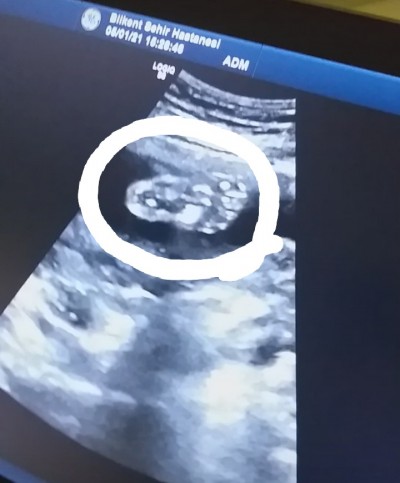

Kızlar bugün ayrıntılı ultrasona gittim bebegimin ayaginin resmini çektim banada resim olarak bebişimin pipisinin resmini verdi doktor hanım:)))

Dikkatli bak sadece ayagi ve ayak parmakları var:)) paşamın